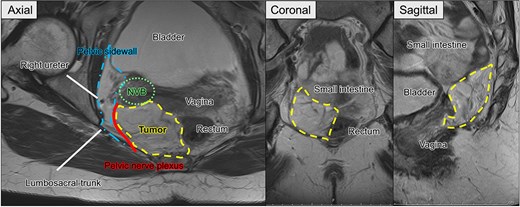

Preoperative pelvic MRI showing the extent and anatomical relationships of the recurrent tumor (dashed line). Axial view: The tumor is located adjacent to the rectum and vagina, abutting the pelvic sidewall (dash-dotted line), neurovascular bundle (NVB) (dotted line), pelvic nerve plexus (solid line), and right ureter. Coronal and sagittal views. The tumor is observed near the small intestine, rectum, bladder, and vaginal stump.